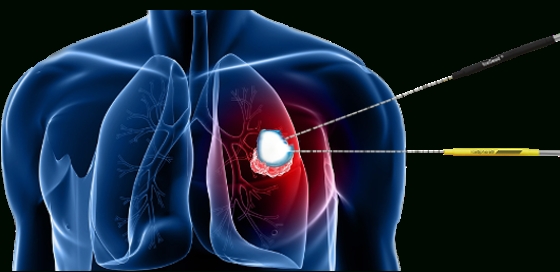

Kriyoablasyon, kanseri tedavi etmek için soğuk(-40C) kullanan bir prosedürdür.

Kriyoablasyon sırasında, kriyoprob adı verilen ince bir iğne deriye batırılır ve kanserli bölgeye aktif olan yani soğutulabilen uç kısmı tümör merkezine yerleştirilir. Kriyoprob doğrudan kanserin içine yerleştirilir. Dokuyu dondurmak için kriyoprobun içine bir gaz pompalanır. İğnenin sadece uç kısmı aktiftir ve istenilen kadar bir alanı soğutur. Kanserli doku ilk kez dondurulduktan sonra sonra doku çözülmeye bırakılır. Dondurma ve çözme işlemi bu şekilde birkaç kez tekrarlanır.

- Akciğer kanseri.